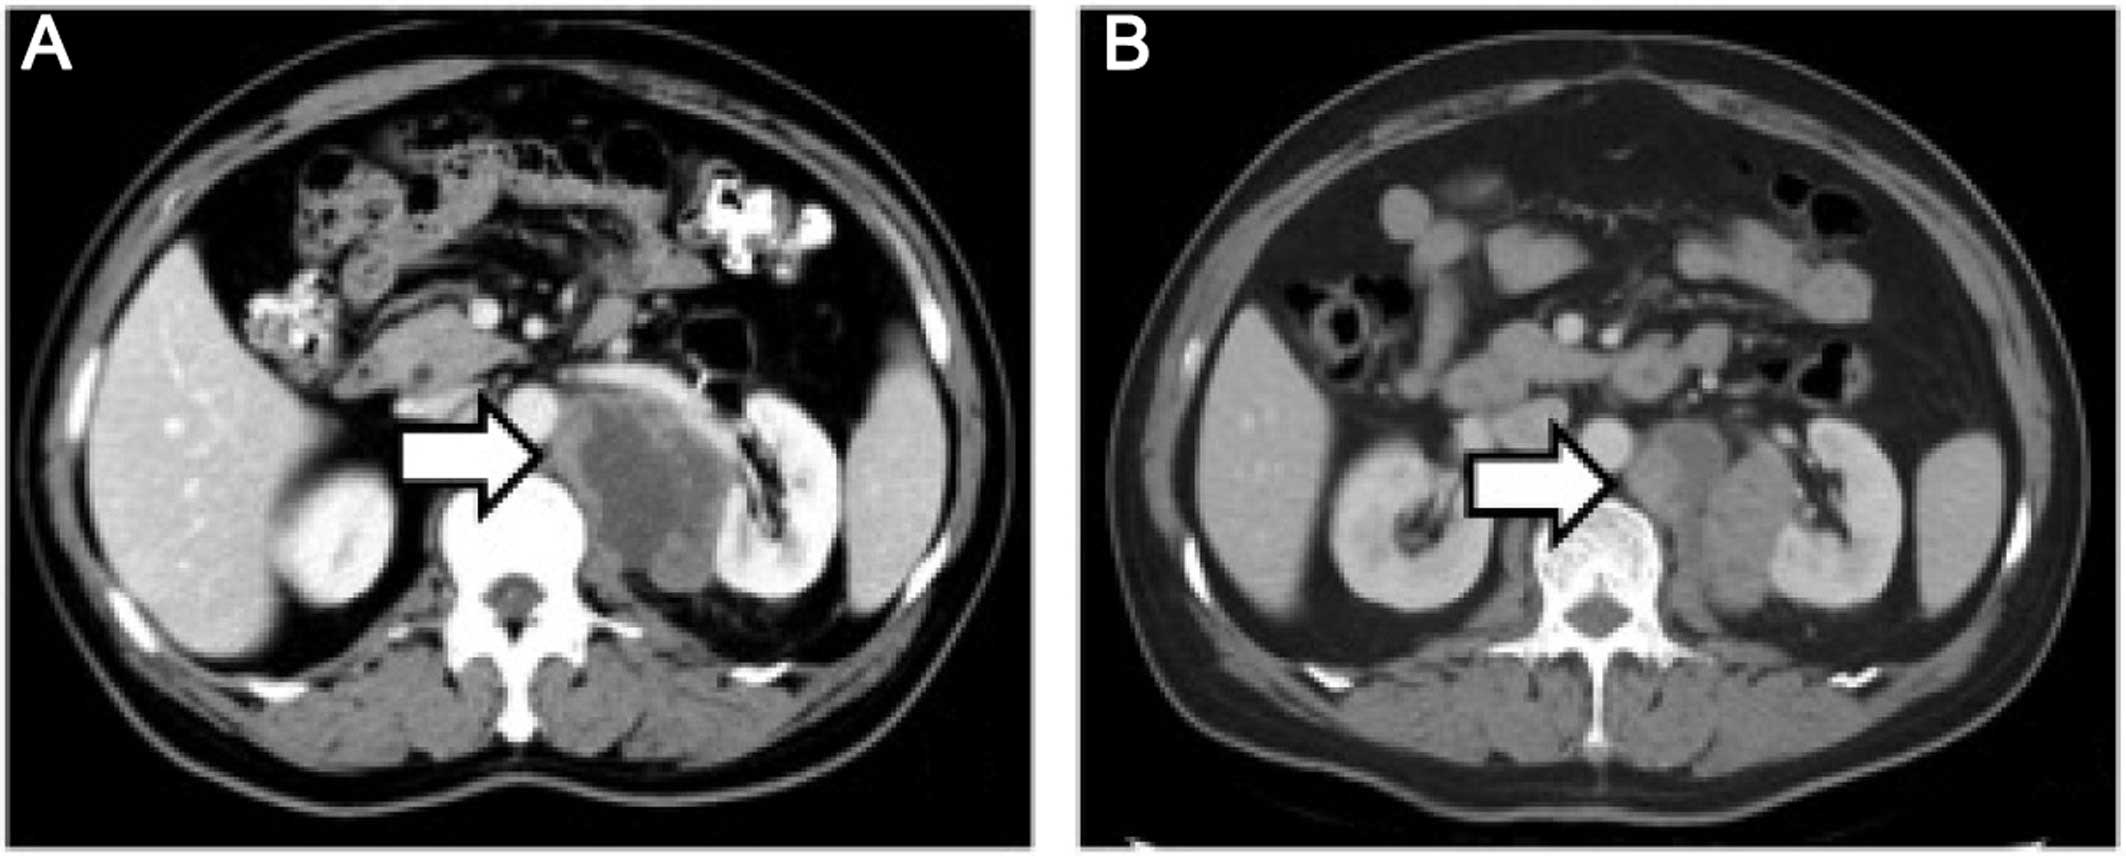

Retroperitoneal Leiomyosarcoma. - Body MR Case Studies - CTisus CT Scanning

www.ctisus.com

www.ctisus.com

ct leiomyosarcoma retroperitoneal ctisus mr body diagnosis studies case

Retroperitoneal Leiomyosarcoma From The Radiologic Pathology Archives

pubs.rsna.org

pubs.rsna.org

leiomyosarcoma retroperitoneal pathology radiologic archives rg